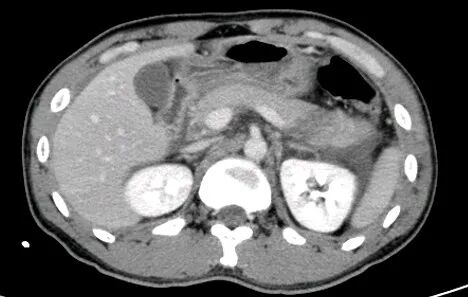

胃癌

进展期胃癌CT检查有利于观察病变的侵犯范围和淋巴结转移情况

早期胃癌多数病人无明显症状,少数人有恶心、呕吐或是类似溃疡病的上消化道症状。疼痛与体重减轻是进展期胃癌最常见的临床症状。病人常有较为明确的上消化道症状,如上腹不适、进食后饱胀,随着病情进展上腹疼痛加重,食欲下降、乏力。

升结肠癌并肝转移